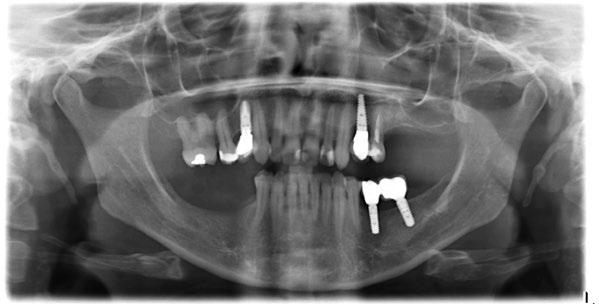

Figura 16. Ortopantomografía postoperatoria.